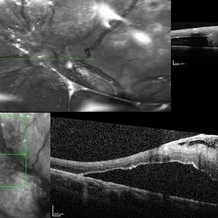

Fibrosis and Traction Following Traction Retinal Detachment Repair

Oct 13 2020 by Sophia El Hamichi, MD

A 29-year-old female with a history of diabetes mellitus type 1, presented with proliferative diabetic retinopathy OU and tractional retinal detachment OD. The patient underwent retinal detachment repair with pars plana vitrectomy, endolaser and silicone oil placement. After one month of her surgery, the patient presented with retinal fibrosis and traction. The image on the top shows the OCT of the fibrosis post op, that was not present in the pre op (OCT image on the bottom).

Photographer: Belinda Rodriguez, Murray Ocular Oncology and Retina, Miami

Condition/keywords: optical coherence tomography (OCT), pars plana vitrectomy (PPV), proliferative diabetic retinopathy (PDR), proliferative vitreoretinopathy (PVR), tractional retinal detachment